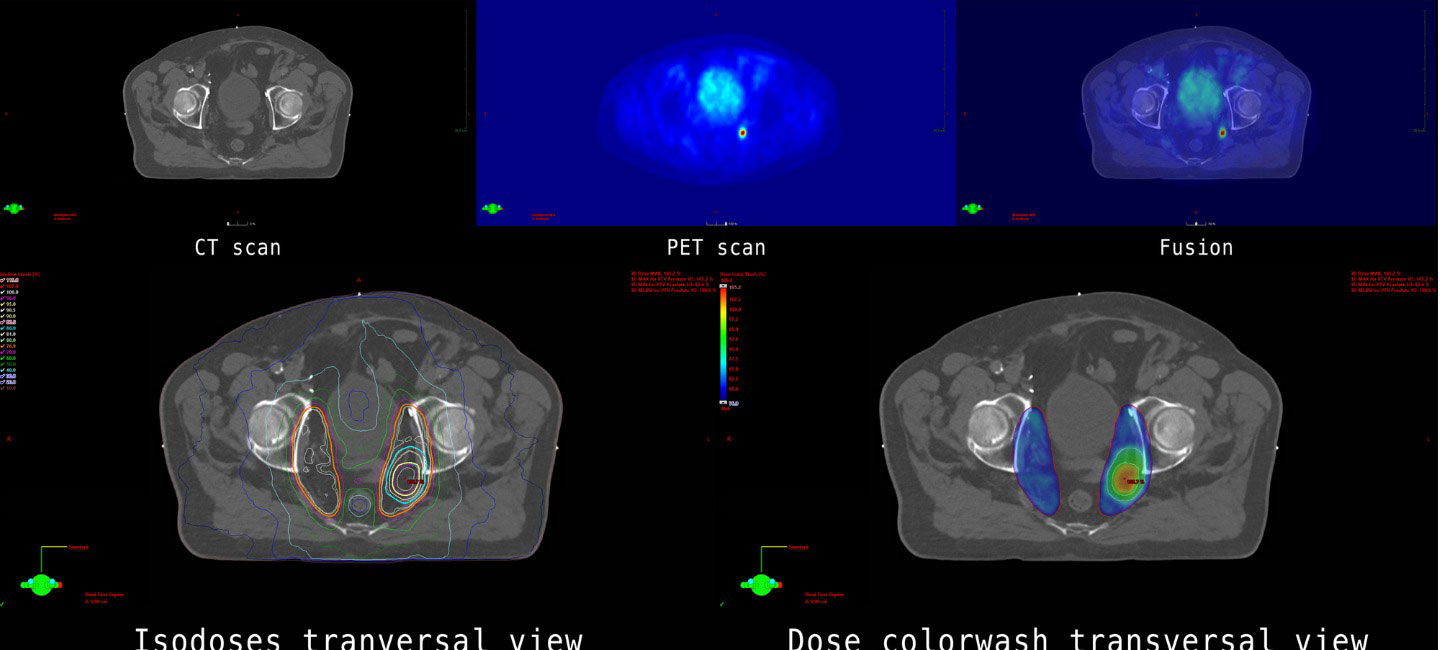

The PACE B (Prostate Advances in Comparative Evidence) study highlights the benefits of stereotactic body radiation therapy (SBRT) for prostate cancer patients. The phase 3 randomized study found SBRT performed as well as standard treatment with moderately fractionated radiation for patients with localized disease. SBRT was delivered in high doses over five treatment sessions, compared to conventional lower dose radiation therapy delivered over several weeks. The five-year disease control rate was 96% with SBRT and 95% for conventional radiation.

“At Moffitt, we preferentially opt for SBRT for men with few significant urinary symptoms and who have smaller prostate glands (<60cc).  We have found this population does very well with SBRT of five fractions over 10 days, especially when MR guidance and gel spacers are used,” said Dr. Peter Johnstone, vice chair & clinical director of the Department of Radiation Oncology at Moffitt Cancer Center.